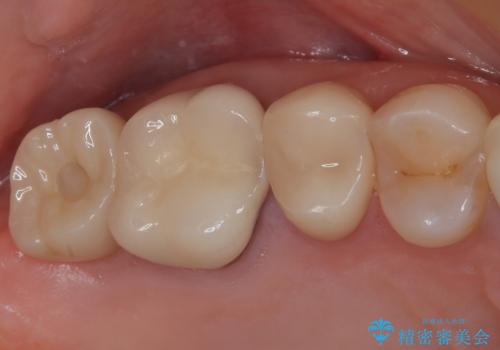

奥歯の目立つ銀歯をセラミックに オールセラミッククラウン治療

【審美修復】被せ物のみの治療

担当医 河口智英